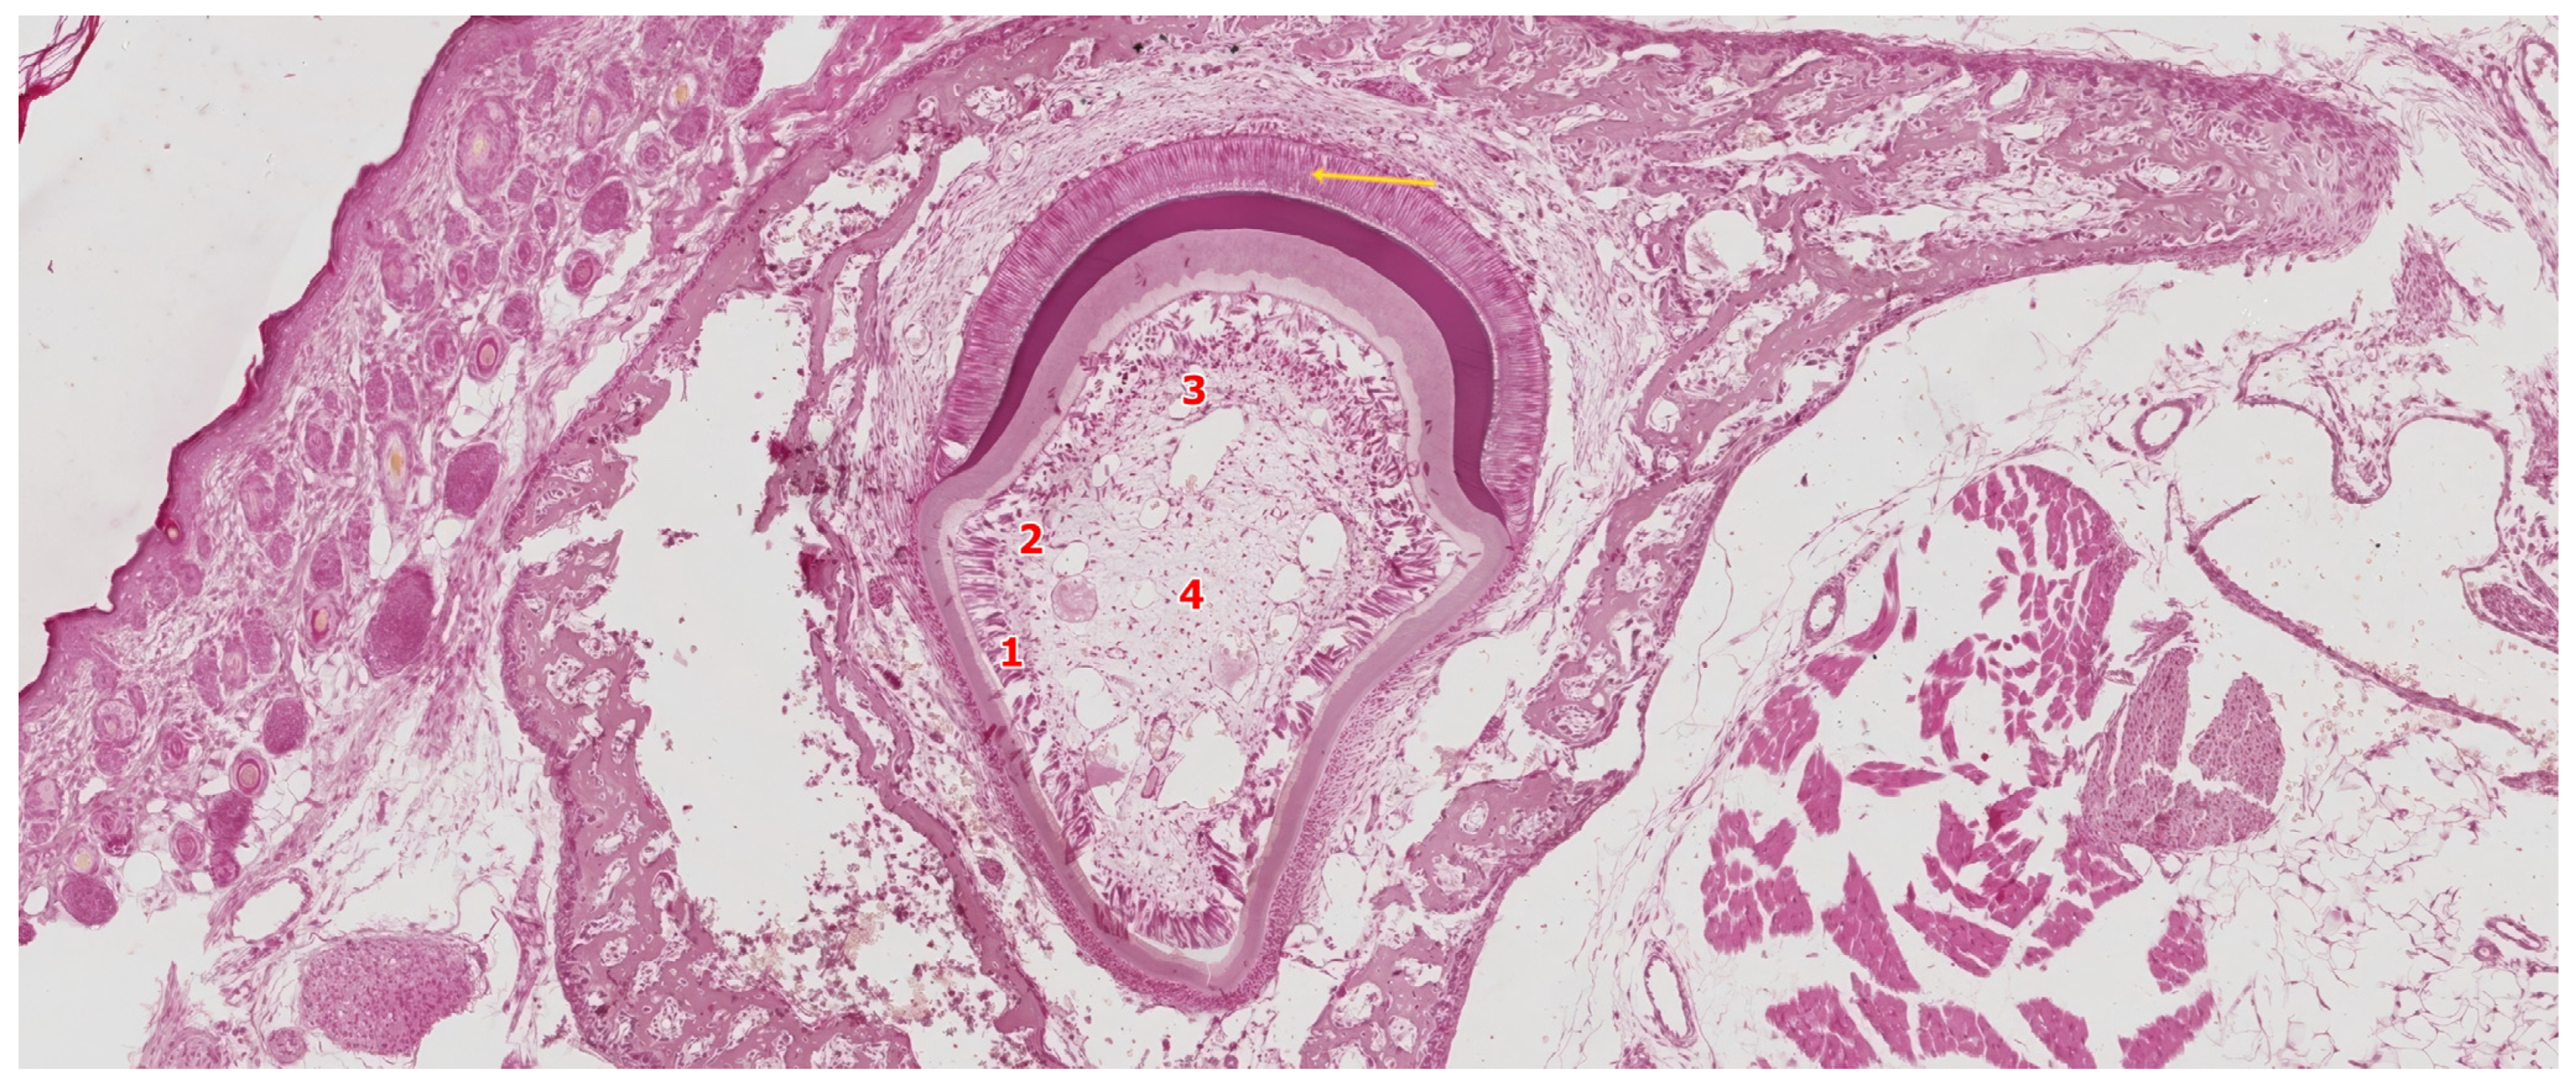

3.3.2. Late Bell Stage

Differentiation of Odontoblasts

Differentiation of Ameloblasts

3.4. The Crown Stage—Apposition